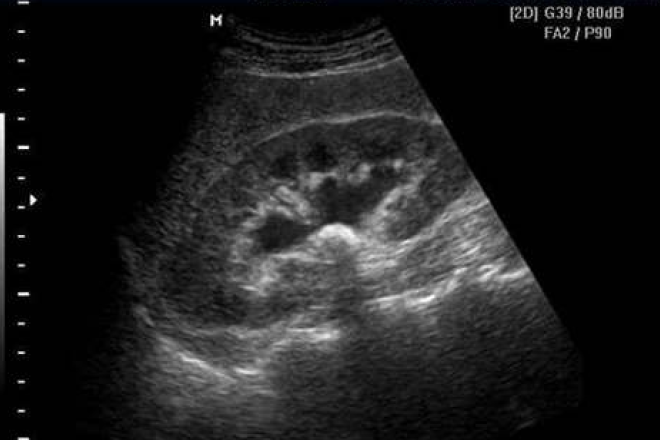

Cirrosis hepática.

Estadio final de todas las enfermedades hepáticas crónicas progresivas, caracterizado por pérdida del parénquima hepático, formación de septos fibrosos y nódulos de regeneración estructuralmente anormales, dando lugar a una distorsión de la arquitectura hepática normal y alteración de la anatomía de la vascularización hepática y de la microcirculación. Cuando se